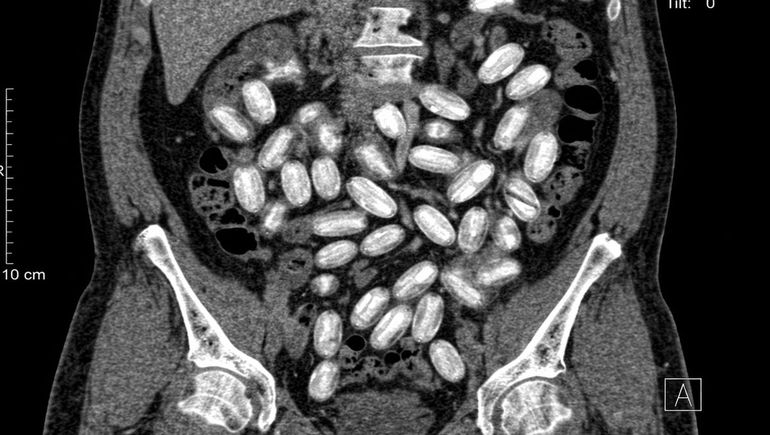

Los resultados confirmaron las sospechas: seis personas transportaban cápsulas de cocaína dentro de sus cuerpos. Bajo supervisión médica y con protocolos sanitarios, los involucrados comenzaron a expulsar los envoltorios.

En total, se contabilizaron 502 cápsulas, con un peso que superó los seis kilos. Cada una pesaba entre 11 y 12 gramos. Según fuentes del caso, cada “mula” habría ingerido alrededor de 80 cápsulas, una práctica que implica un riesgo extremo para la salud.

El caso expone una modalidad conocida dentro del narcotráfico: el uso de personas como transportistas humanos, conocidos como “body-packers” o “mulas”. En muchos casos, se trata de individuos en situación de vulnerabilidad económica, captados para realizar este tipo de tareas a cambio de dinero.

El traslado mediante cápsulas ingeridas representa uno de los métodos más peligrosos. Una ruptura en el interior del cuerpo puede provocar una intoxicación letal en pocos minutos. Aun así, las organizaciones continúan utilizando este sistema por su eficacia para evadir controles.